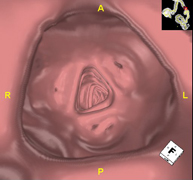

- Virtual colonoscopy

Virtual colonoscopy is a non-invasive technique that allows three-dimensional and two-dimensional visualisation of the large intestine or colon by taking sequential images captured with a state-of-the-art MDCT scanner. The quality of the images allows virtual navigation through the rectum and colon thanks to processing on specialised workstations. Preparation for the test consists of following a low-fibre diet for three days before the test (to cleanse the colon and rectum) and ingesting an iodinated oral contrast agent the day before the test (to mark the stool so that it can be correctly distinguished from any colonic lesions). Unlike fibrocolonoscopy, no sedation or bowel preparation is required. The test is performed in the CT room, where air is blown through a small flexible tube to distend the colon.